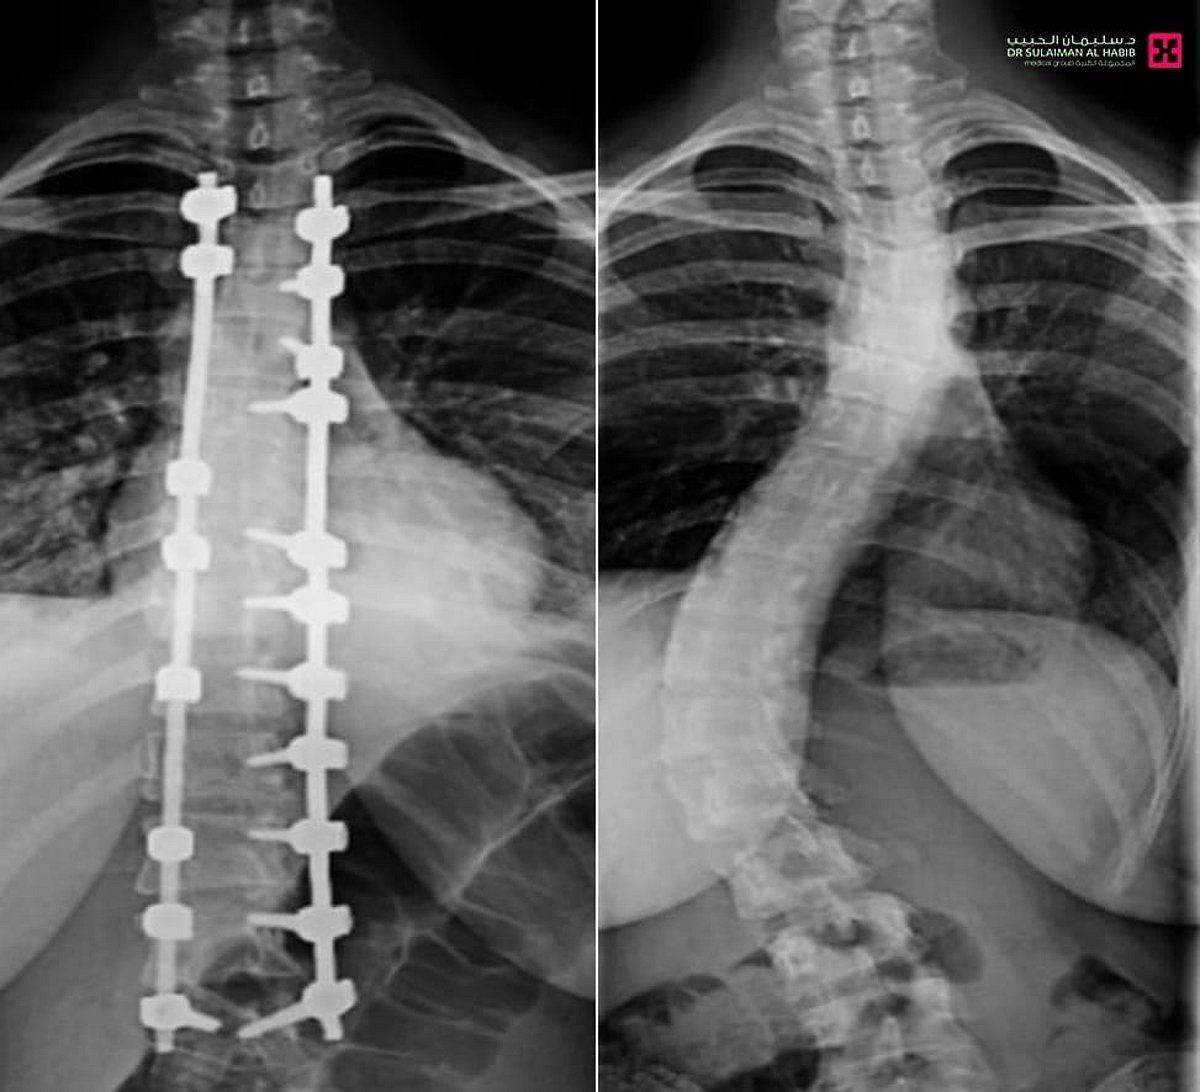

تمكّن فريق طبي في مستشفى الدكتور سليمان الحبيب بالصحافة، من إجراء عملية نوعية ناجحة لتقويم تشوّه متطور بالعمود الفقري لشابة عشرينية، كانت تعاني من ميلان (جنف) بدرجة "55" وتحدّب صدري بمقدار "70" درجة، ما سبّب لها صعوبات في الجلوس والمشي بشكل مستقيم، وأثّر سلبًا على حياتها الاجتماعية والنفسية، ذكر ذلك د. تركي العنزي استشاري المخ والأعصاب وجراحات العمود الفقري المعقّدة، رئيس الفريق الطبي المعالج.

وأوضح د. العنزي أن المراجعة خضعت فور وصولها للمستشفى لفحوصات دقيقة، شملت الأشعة السينية والرنين المغناطيسي، والتي أظهرت وجود ميلان وتحدب متزايد يتطلب تدخلاً جراحيًا عاجلًا.

وأضاف أن العملية استغرقت "5" ساعات، وأُجريت تحت المراقبة العصبية الدقيقة، وشملت تصحيح العمود الفقري على امتداد "12" فقرة عبر تثبيتها ودمجها باستخدام أحدث أنظمة التثبيت الجراحي، مع إغلاق تجميلي للجرح بتقنيات متقدمة تضمن تقليل الآثار مستقبلاً، إضافة إلى إعادة توازن الكتفين وتناسق الخصر، وأسهم في نجاح العملية توفّر أحدث الأجهزة الطبية وكوادر طبية وتمريضية عالية التأهيل.